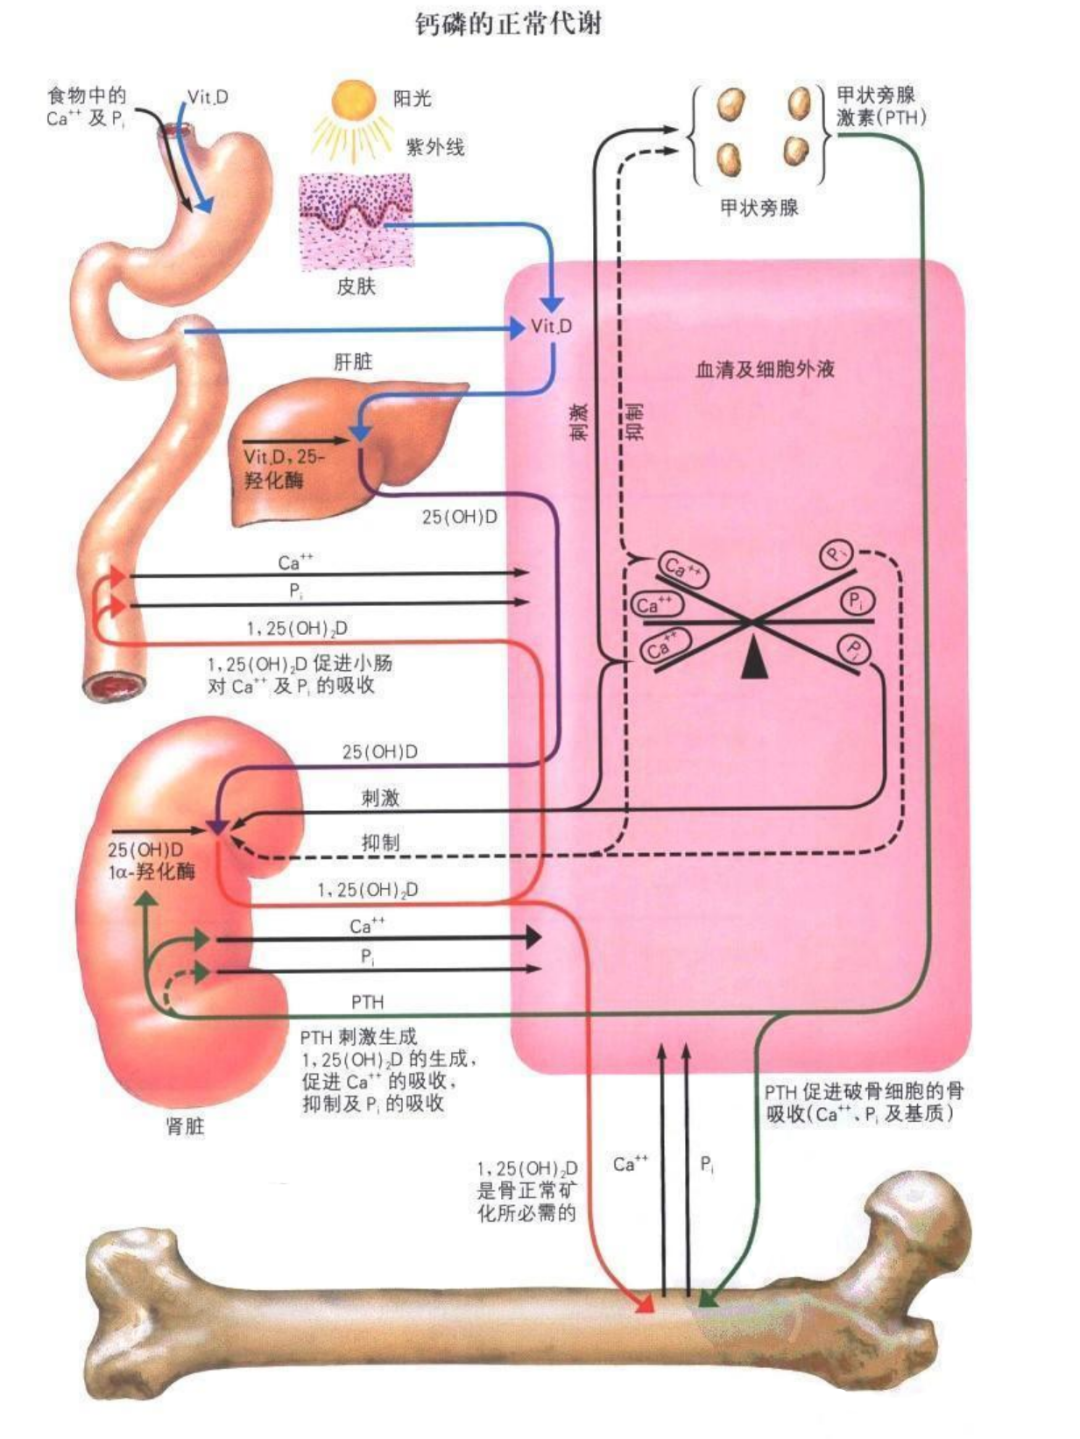

维生素 D 除了来源于食物,还依靠阳光中的紫外线照射皮肤而合成。

5、保护肝肾功能

有利于活性维生素 D 的形成,有利于骨骼的矿化。

2、维生素 D(骨活化剂)

骨质疏松患者负钙平衡的原因之一是肠道对钙的吸收障碍。

具有活性的维生素 D 能加强肠道内钙磷的吸收,调节 PTH 分泌及骨细胞的分化,促进骨形成;与钙剂合用时,剂量宜小,防止高钙血症的发生。

维生素 D 经肝、肾羟化后形成 1,25(OH)2D3 为最终活性物质,直接参与骨矿物质代谢。

老年人一般维生素 D 吸收代谢(羟化)功能下降,影响钙的吸收,应适当补充。老年人每日维生素 D 摄取量为 400~800 U。